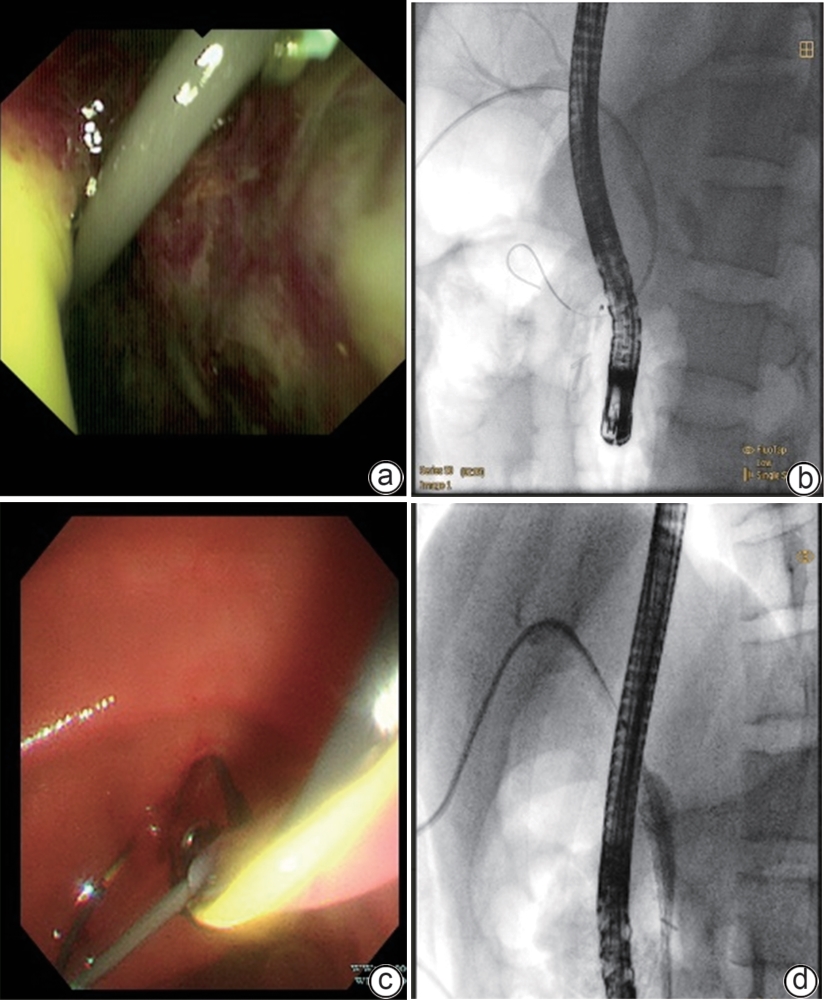

Successful treatment of biliary fistula after Beger surgery by oral choledochoscopy-assisted percutaneous-endoscopic rendezvous technique: A case report

Yuxin WANG, Weigang GU, Zheng JIN, Xiaofeng ZHANG

2025, 41(2): 333-336. DOI: 10.12449/JCH250220

Abstract(845) HTML (244) PDF (4794KB)(48)

Abstract:

Duodenum-preserving pancreatic head resection, also known as Beger surgery, has a high incidence rate of bile duct injury after surgery, while the treatment modality for bile duct injury depends on the severity of the injury, and endoscopic therapy is often challenging in case of severe bile duct injury. Recently a patient with biliary fistula after Beger surgery was admitted to Affiliated Hangzhou First People’s Hospital, Westlake University, and successful diagnosis and treatment were achieved through oral choledochoscopy-assisted percutaneous-endoscopic rendezvous technique.